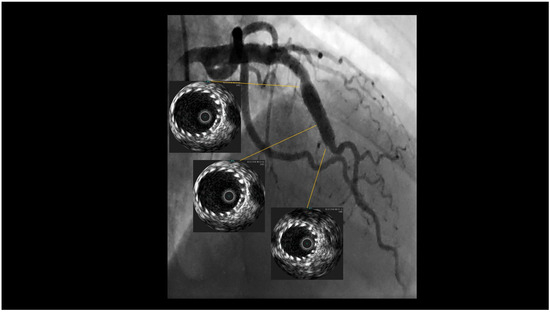

When performing revascularisation of a chronic total occlusion, contralateral injection is essential to visualise the distal bed of the occluded vessel, adding to procedural success. Here we describe a case of antegrade recanalisation of a left anter...